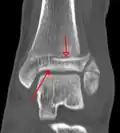

-

A triplane fracture of the ankle as seen on CT